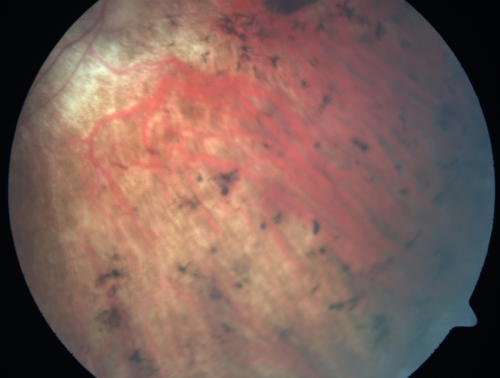

Retinitis Pigmentosa - RP1 Mutation

78 year old man: 20/32 OD and 20/50 OS - RP1 Gene is Bad -- > RP with Novel Amino Acid Change in GLY723Stop sequence of the RP1 gene - consistent with AD RP